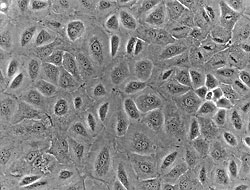

Human mesothelial cells in culture